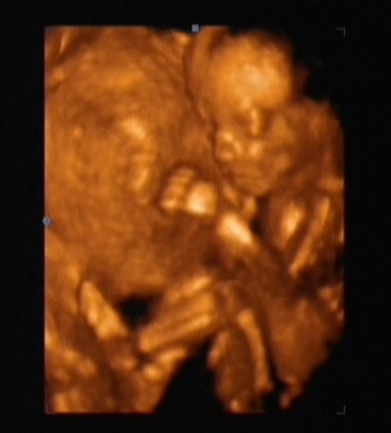

Ezek után gyors kaja, aztán rohanás le a dokinénihez egészséges tanácsadásra. Lili megkapta a második kötelező oltását. Nagyon jól viselte, lehet, hogy azért mert az apukája is ott volt vele, és fogta a kezét.

6080 gramm, és 60 centi. Minden rendben van vele szerencsére.